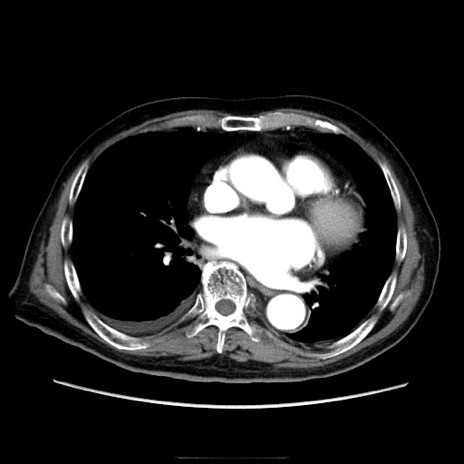

症例21(横断像)

【症例】70歳代男性

【主訴】腹痛

【現病歴】肝硬変・肝細胞癌にてかかりつけの方。約9時間前に食後より腹痛出現。症状が徐々に増悪し、嘔吐出現したため来院。

【既往歴】肝硬変、肝細胞癌(RFA、TACE後)

【身体所見】意識清明、表情苦悶様、BT 36℃、BP 129/78mmHg、P 88bpm、SpO2 97%(RA)、右上腹部から心窩部にかけて圧痛あり、反跳痛なし、筋性防御あり。

【データ】WBC 5800、CRP 0.16